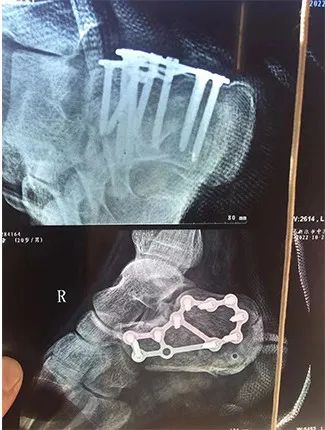

足跟粉碎性骨折

被植入多根钢钉